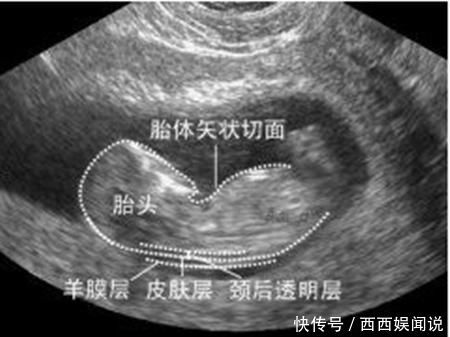

第一次:怀孕12周的NT检查

NT检查是最早的排畸检查,主要评估胎儿唐氏综合征的风险,准确率很高。

最佳检查时间是怀孕11-14周,但怀孕12周是第一次正规产检,所以一般医生也就建议和这次产检一块儿做了。

“NT”指的是颈后透明层,在产检结果中会有一个数值,但这个数值并不是越小越好,而是有正常范围,低于3毫米就表示胎儿正常。